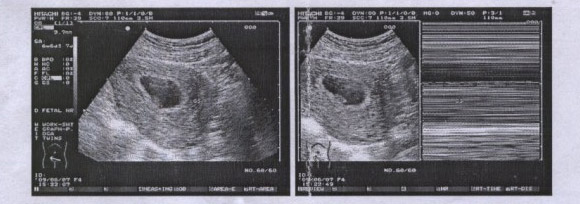

人流术前必须经过hcg或B超确认为宫内孕

确认受孕天数和孕囊大小适合做人流手术才可以

一般在怀孕35-49天左右可进行手术,此时子宫不太大,胎儿及胎盘尚未形成,容易将胎块组织吸出。